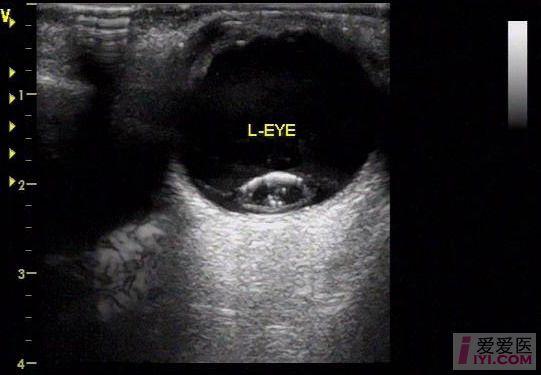

晶状体半脱位